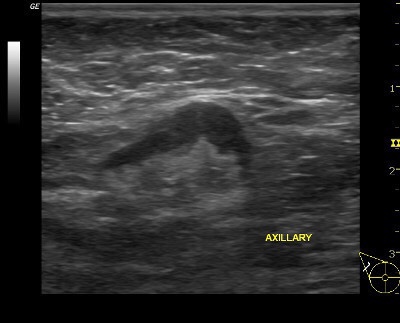

👉Reactive nodes can be difficult to distinguish from metastatic nodes (Image).

👉In general, benign causes of nodal enlargement tend to thicken the cortex diffusely.

👉In addition, it is not uncommon to have a metastatic node adjacent to a normal node, but all nodes in a region tend to be reactive when the cause is benign.